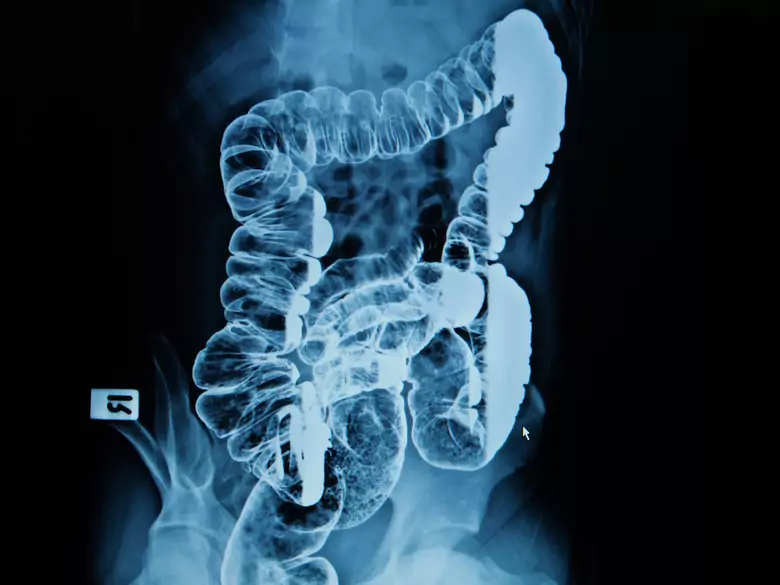

Intestines